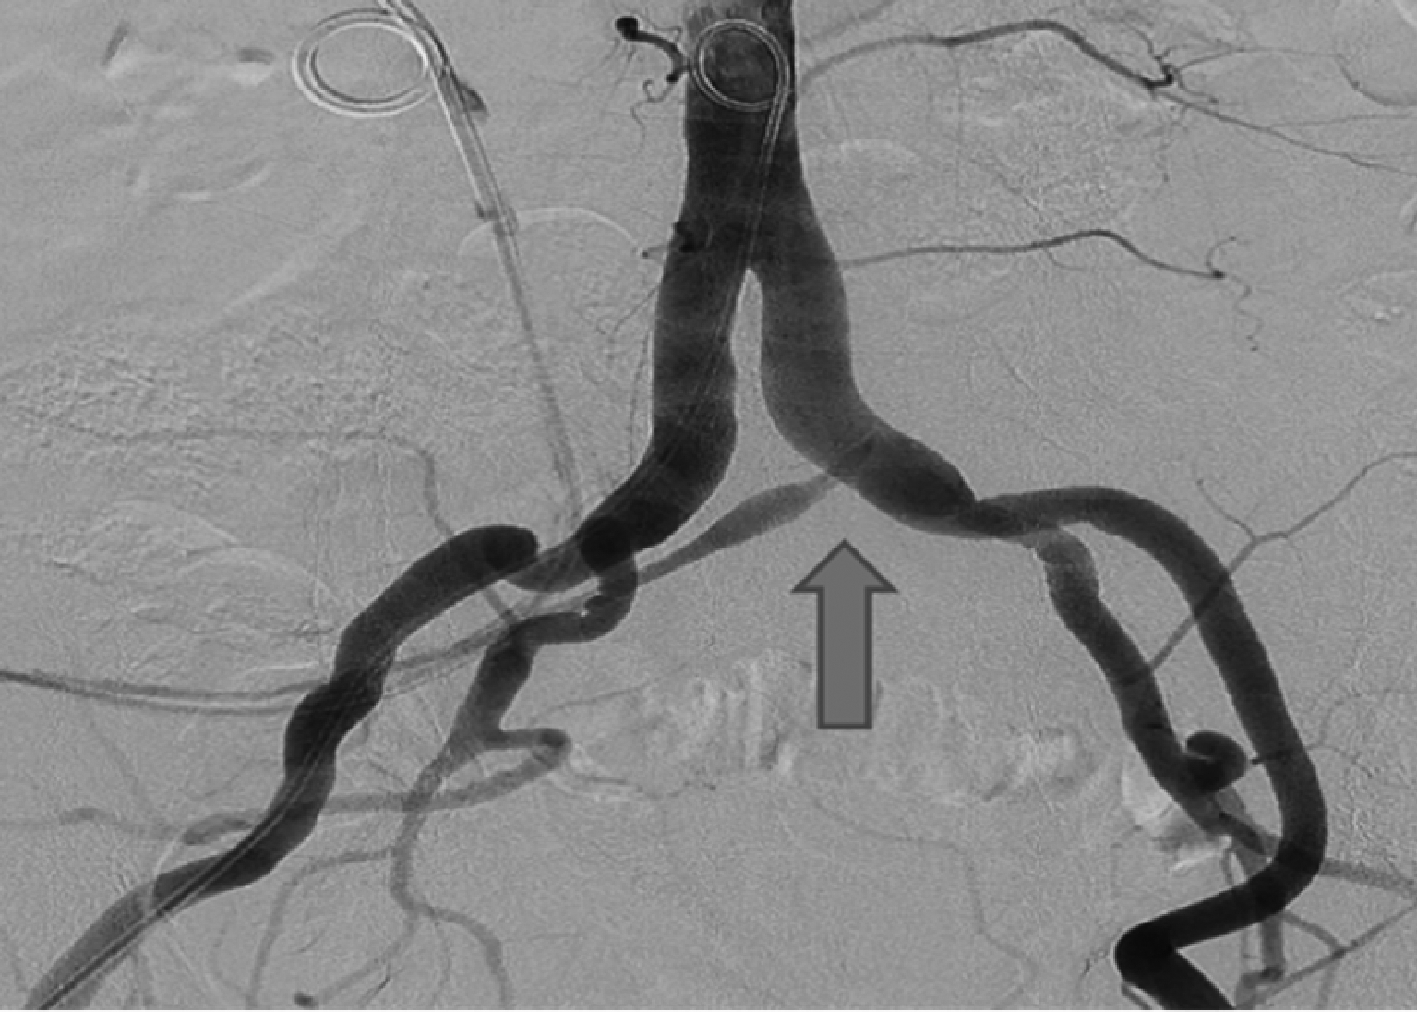

图1

髂总动脉输尿管瘘的血管造影"